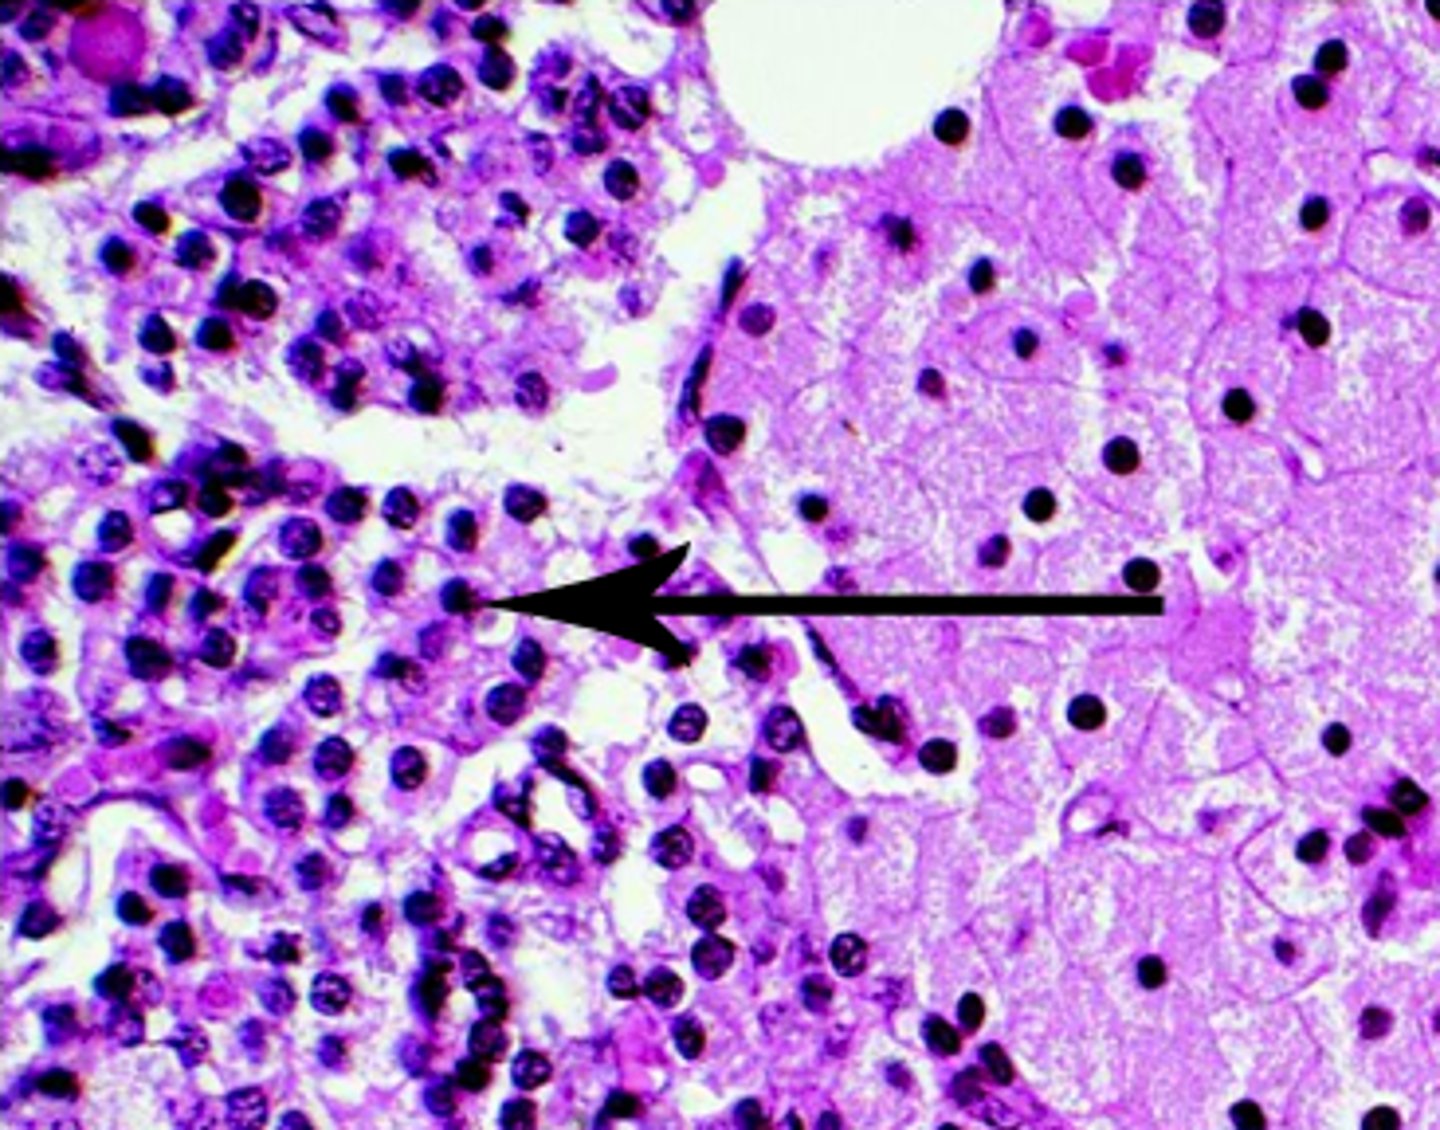

alpha cells of pancreas (produce glucagon)

beta cells of pancreas (produce insulin)